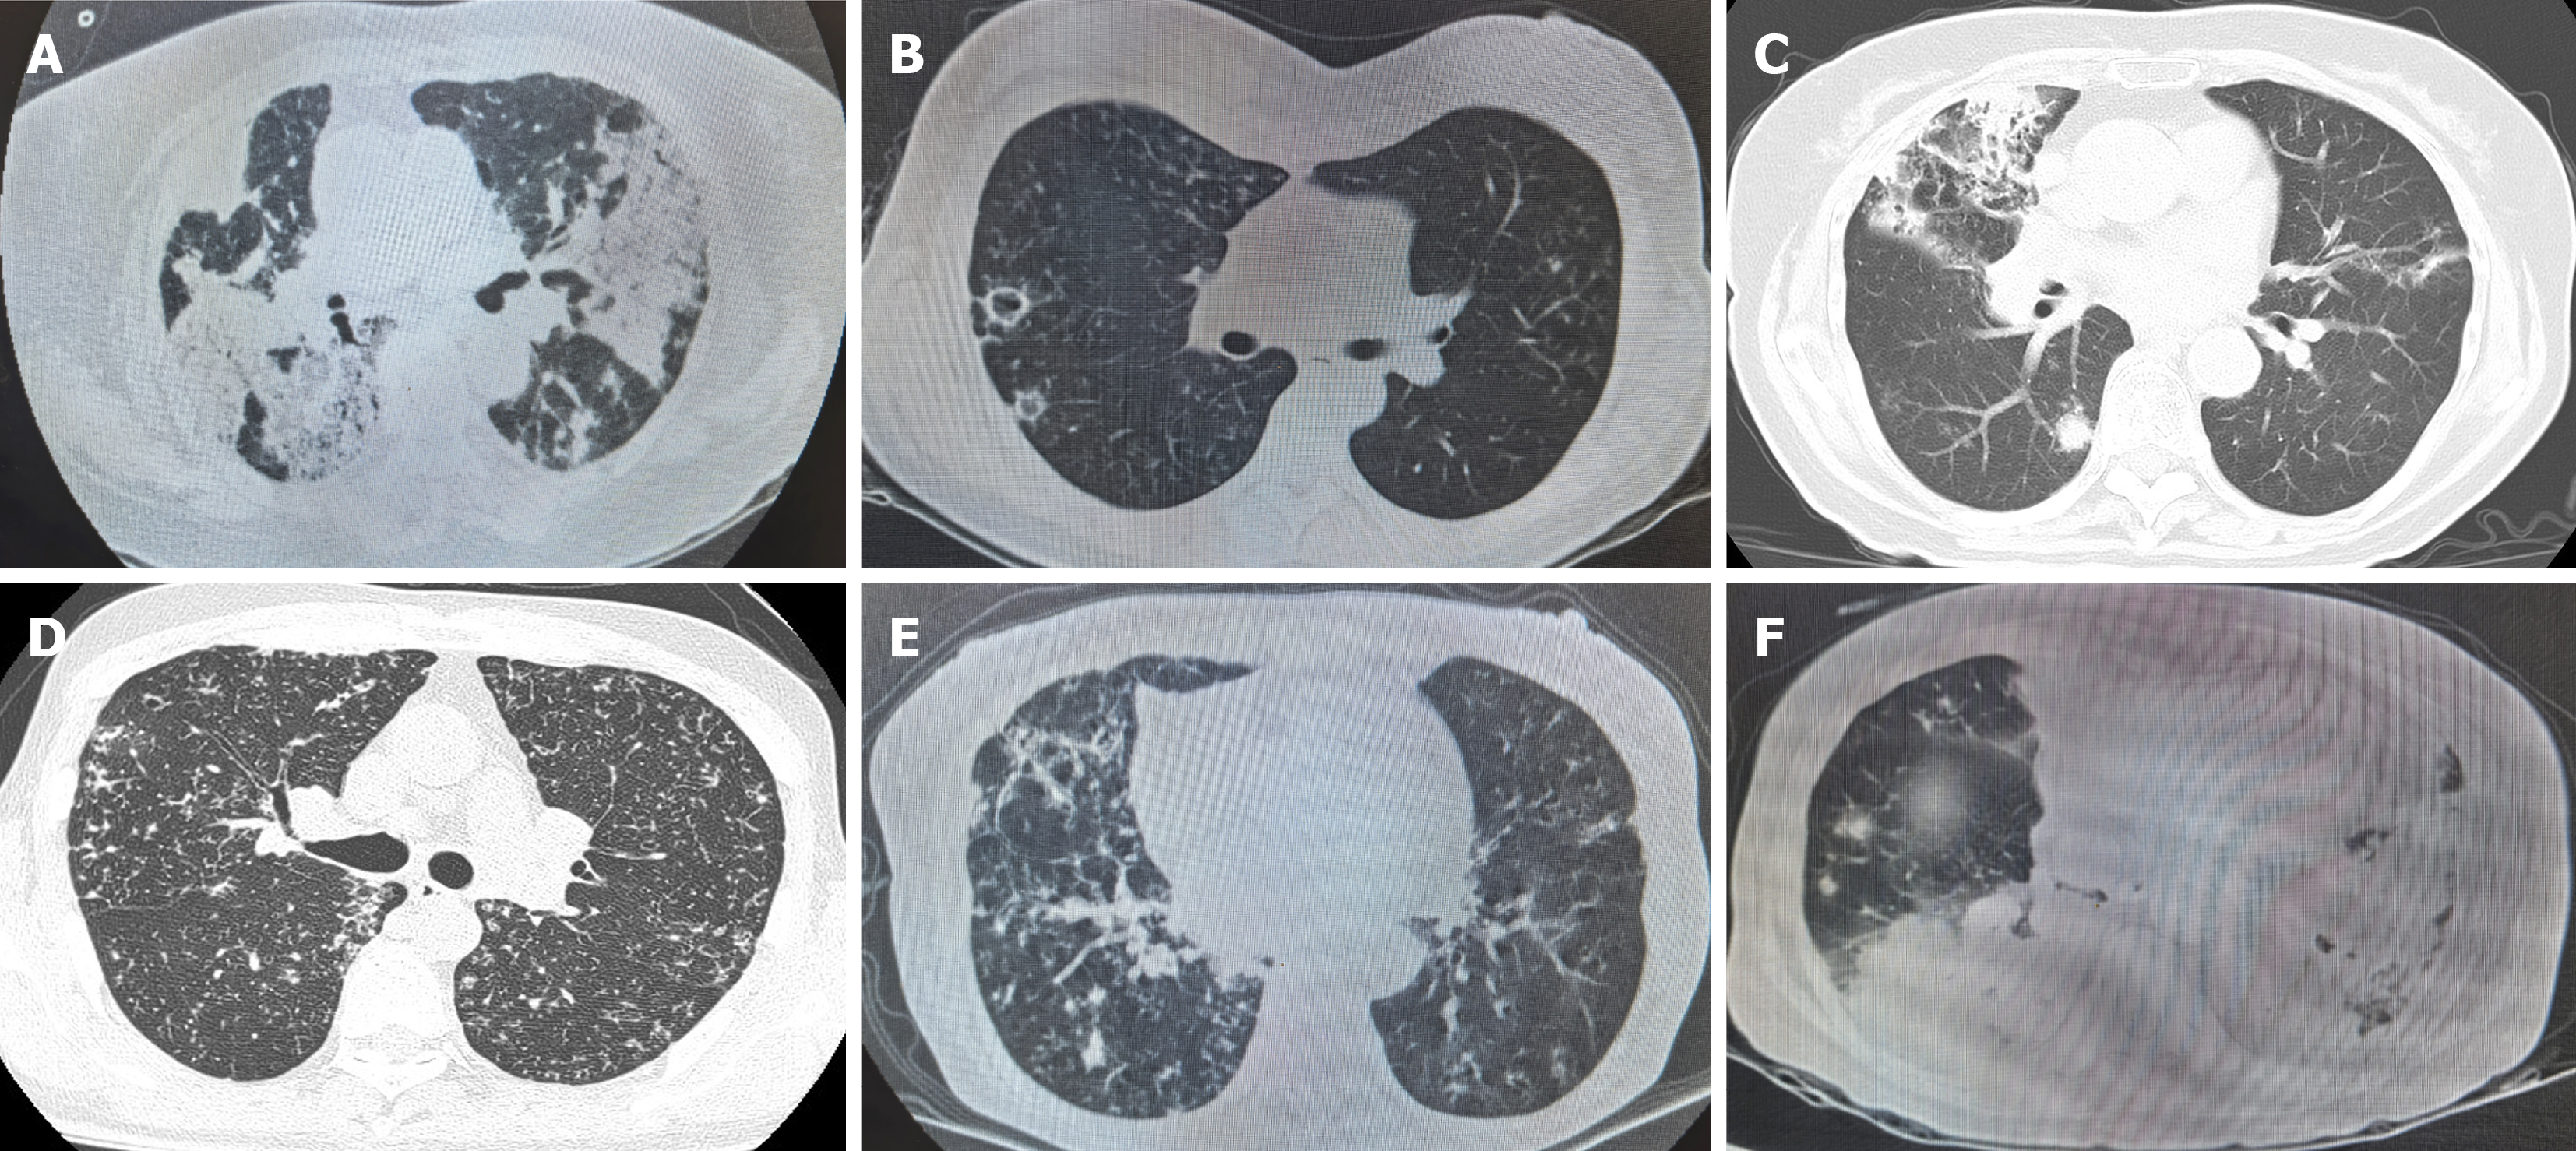

Figure 2 Chest computed tomography features of pulmonary nocardiosis caused by different species.

A: Immunosuppression; B: Nocardia gelsenkirchenensis; C: Nocardia cyriacigeorgica; D: Nocardia wallacei; E: Nocardia abscessus; F: Nocardia farcinica.